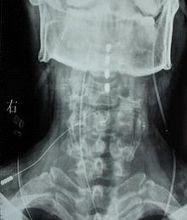

昏迷促醒圖為植入後的X線片,可見植入到高頸段的點狀電極